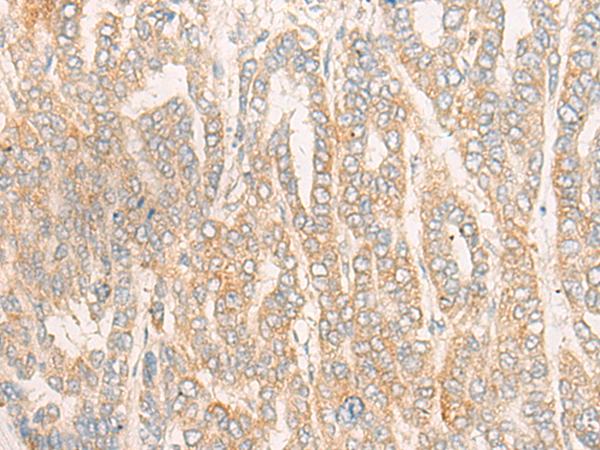

IHC Positive control: |

Human gastric cancer;Human liver cancer |